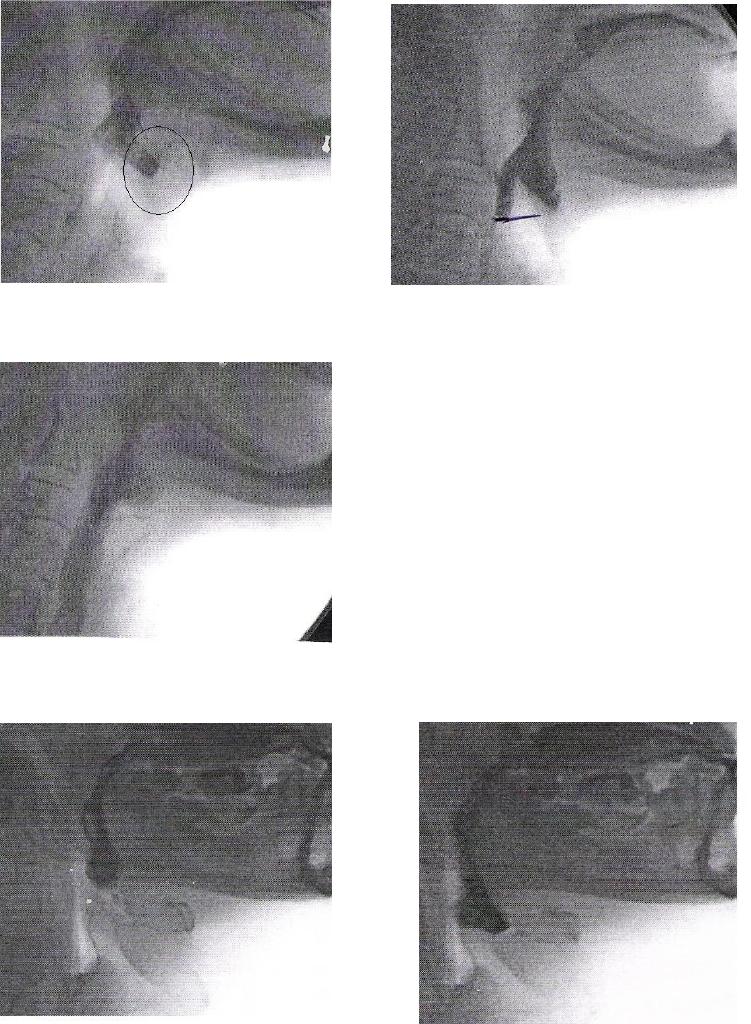

ANEXO E Imagens videofluoroscópicas da deglutição, registrando

escape prematuro e reação de deglutição atrasada, p e s

crioestimulação, com líquido e pastoso.........................................................